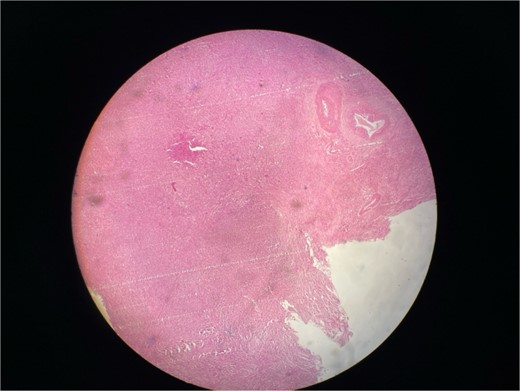

Gross examination revealed mass along GB 5 × 2 × 1 cm and attached 5 × 4 × 2 cm liver. Cut section of GB mucosa is velvety and fundus is thickened measuring 1.2 cm. Histopathology report revealed polygonal eosinophilic cells with granular cytoplasm strongly positive for periodic acid-Schiff (PAS) (Figs 3 and 4). These cells also contain vesicular small centrally located nucleus which appears in clusters or sheets and infiltrated diffusely within the surrounding structures suggesting of Granular cell tumor. All the margins were negative for tumor. Liver was unremarkable, so were the regional lymph nodes. Immuno-histochemistry confirmed CD 68 positivity and negative for SOX10, CK, SMA, desmin, Ki-67 favoring the neural origin of the tumor further enhancing the diagnosis (Figs 5 and 6).

High resolution image shows polygonal cells with granular cytoplasm with vesicular small centrally located nucleus.

Microscopically these tumors contain granular eosinophilic cytoplasm with vesicular nucleus where granules are positive for periodic-acid Schiff’ staining. They appear in cluster or sheets. They infiltrate surrounding tissue diffusely separated by thin connective tissue. Mitoses are rare. No necrosis is present. Reactive atypia of the overlying epithelium and metaplastic pyloric gland may mimic carcinoma [7, 9, 10]